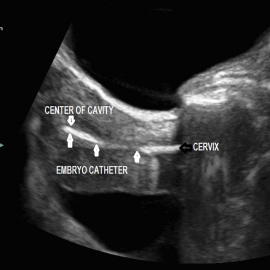

إرجاع الأجنة إلى الرحم

حيث تعاد الأجنة إلى الرحم بعد يومين إلى ثلاثة (وفي بعض الحالات بعد خمسة أيام عند الرغبة بالوصول إلى مرحلة العلقة أو الكيسة الأرومية Blastocyst) وذلك بطريقة سهلة غير مؤلمة وتتم دون الحاجة إلى تخدير إلا في حالات خاصة جدا.